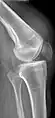

An x-ray demonstrating quadriceps tendon rupture. Note the abnormal angle of the patella and soft-tissue swelling marked by the arrow.

A quadriceps tendon rupture is a tear of the tendon that runs from the quadriceps muscle to the top of the knee cap.[1]